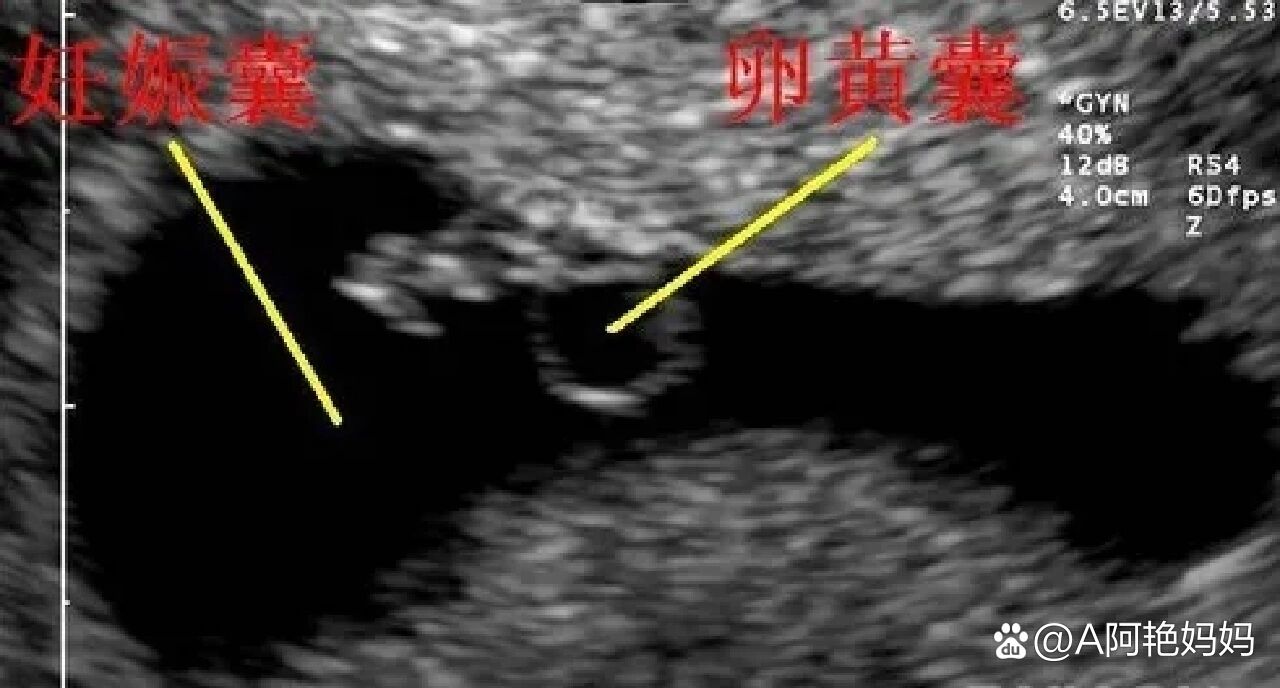

卵黄囊是子宫内妊娠囊内一个包含液体的小囊,在怀孕早期通过超声检查可清晰观察到其主要功能是为早期胚胎提供营养和激素支持,是胚胎发育的关键结构之一当超声显示一个卵黄囊时,医生会结合以下指标综合判断1 正常宫内妊娠若孕囊内同时可见胎芽和胎心搏动,通常提示胚胎发育正常,怀孕成功此时卵黄;囊内可见卵黄囊是指在孕囊内检测到卵黄囊结构,这一发现对评估胚胎发育具有重要科学意义,具体体现在以下方面1 胚胎发育进程的重要标志卵黄囊是早期胚胎发育的关键结构,通常在孕56周通过超声首次观察到其出现表明胚胎已进入正常发育轨道,是妊娠早期的重要里程碑若在预期时间内未检测到卵黄囊。

“囊内可见卵黄囊”是超声检查中判断宫内早孕的重要依据,其意义可从以下三方面理解1 确认宫内妊娠的关键标志卵黄囊是胚胎发育早期形成的囊性结构,通常在孕5周左右通过超声首次观察到其存在直接证明受精卵已着床于子宫腔内,可排除宫外孕等异常妊娠情况临床诊断中,仅当超声图像明确显示孕囊内存在;“囊内见卵黄囊”是B超检查中提示妊娠的重要依据具体分析如下1 医学定义与妊娠确认卵黄囊是胚胎发育早期形成的囊状结构,位于妊娠囊内其出现是妊娠的特异性标志之一,因为并非所有囊性结构都代表妊娠组织只有当囊内观察到卵黄囊胎芽或胎心等妊娠特有结构时,才能确诊为妊娠例如,单纯囊肿或。

囊内见卵黄囊是超声检查中提示宫内早孕的重要表现,具体信息如下卵黄囊的定义与功能卵黄囊是位于孕囊内的早期胚胎结构,是子宫内妊娠的标志性特征其核心功能包括为胚胎提供营养支持参与激素分泌如人绒毛膜促性腺激素,HCG以及血细胞生成,对胚胎早期发育至关重要出现时间与临床意义卵黄囊通常在停经56周时通过阴道超声观察到它;内见卵黄囊是指在超声检查等影像学检查中,观察到孕囊内存在卵黄囊结构这一发现对评估胚胎早期发育情况具有重要意义,具体可从以下几方面理解卵黄囊是孕囊发育过程中的关键结构它通常在孕早期如孕56周出现,是胚胎早期发育的重要营养来源卵黄囊通过分泌营养物质,为胚胎提供初始生长所需的能量。